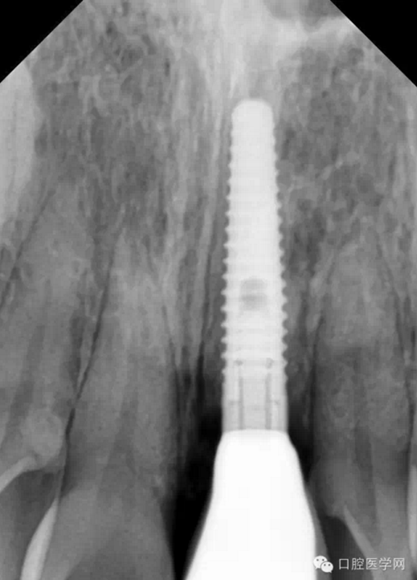

第二種種植體是 NobelReplace系統(tǒng)

X光片顯示為: